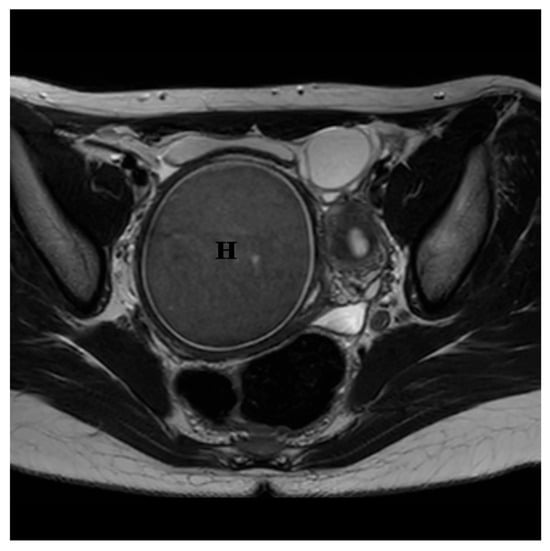

2. Case Presentation